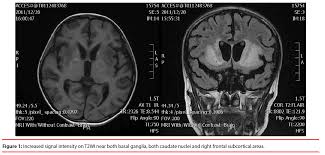

This activity reviews the evaluation and treatment of KBS and highlights. IN 1937 Klüver and Bucy 1 described a striking behavioral syndrome in rhesus monkeys after bilateral temporal lobe ablations. Kluver-Bucy syndrome KBS is a rare neuropsychiatric disorder due to lesions affecting bilateral temporal lobes especially the hippocampus and amygdala.

Klüver-Bucy syndrome is a rare behavioral impairment that is associated with damage to both of the anterior temporal lobes of the brain.